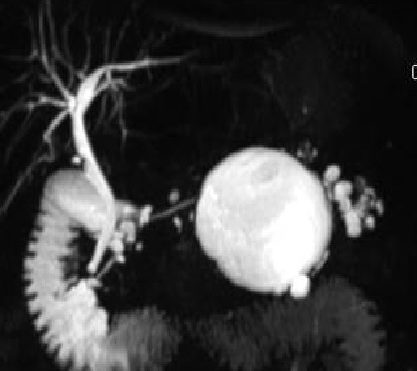

We notice an increasing frequency in the detection and evaluation of pancreatic cystic lesions (PCLs) over the last three decades. They show awide spectrum of imaging and clinical features. The diagnosis and discrimination of these lesions are very important because of the risk for concurrent or later development of malignancy. The main reason is the increased awareness of these lesions and the extensive use of cross-sectional imaging, an always improving technique (1). Commonly, PCLs are diagnosed incidentally during investigation for often unrelated and nonspecific abdominal complaints using state-of-the art abdominal imaging (CT, MRT). The term PCN denotes a histologically heterogeneous collection of neoplasms showing a wide spectrum of diagnoses, ranging from completely benign to potentially malignant, to carcinoma in situ, to frankly invasive and malignant (2,3). In 1978, Compagno and Oertel were the first to recognize the crucial distinction between the serous and the mucinous cystic neoplasms of the pancreas by explaining the importance of identifying the mucinous neoplasms because of their overt or latent malignant potential (4,5). Since then, the interest in PCLs increased markedly, especially so with the recognition of the importance and prevalence of intraductal papillary mucinous neoplasms (IPMNs). Nowadays, PCLs represent a common and often difficult challenge in clinical practice, because of the increase in their detection in asymptomatic patients and our still immature understanding of some aspects of their biologic behavior. Their important differences regarding their outcome and the fact of being increasingly often identified has put a special focus on these neoplasms by surgeons, pathologists, gastroenterologists, radiologists, and oncologists alike. Management of patients with PCNs can be challenging and varies considerably among the various subtypes of PCNs. Their treatment ranges from resection of malignant lesions, to resection and/or surveillance in the case of premalignant lesions, to simple observation in the case of benign or indolent lesions. Under these circumstances, the accurate classification of PCNs becomes crucial. Therapeutic decision making and classification rely mainly on the presenting symptoms and radiologic findings, often without actual histologic tissue. It is of extreme importance to identify suspicious features indicating potential or certain malignancy in order to select the appropriate treatment. The risk of overtreatment (unnecessary pancreatectomy) should he balanced carefully with the risk of under treatment (missing the opportunity to cure a potentially curable malignant or premalignant disease).